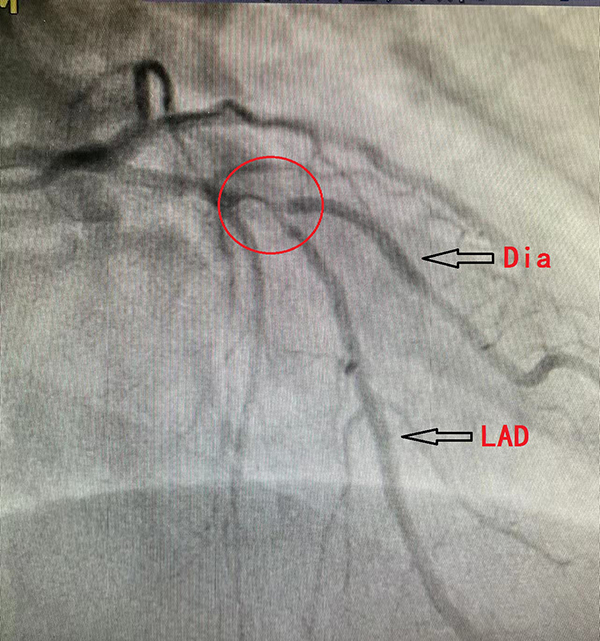

前降支近至中段50-90%弥漫狭窄,第二对角支开口70%局限性狭窄